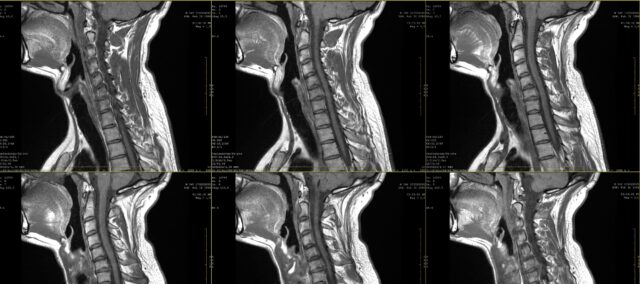

ในโรงเรียน คุณคงเคยเรียนรู้เกี่ยวกับการวาดภาพแสดงอาการเจ็บปวดจากรากประสาทมาบ้างแล้ว อย่างไรก็ตาม ในช่วงทศวรรษแรกของศตวรรษที่ 21 เป็นที่ชัดเจนว่าอาการปวดรากประสาทไม่จำเป็นต้องเป็นไปตามการกระจายตัวของผิวหนังเสมอไป การศึกษาครั้งนี้ต้องการเจาะลึกลงไปถึงความสอดคล้องระหว่างการตรวจภาพความเจ็บปวดจากรากประสาทที่ผู้ป่วยสังเกตเห็นและ MRI ในทางปฏิบัติ ผู้ป่วยมักจะแสดงอาการเจ็บปวดของตนเอง และอาจเสริมด้วยภาพความเจ็บปวด เมื่อสงสัยว่ามีอาการปวดรากประสาท มักจะทำการกำหนดให้มีการตรวจด้วยภาพทางการแพทย์เพื่อตรวจหารากประสาทที่ได้รับผลกระทบและขอบเขตของการมีส่วนร่วมของรากประสาทที่อาจเกิดขึ้น แม้ว่าในหลายกรณีสิ่งนี้จะกลายเป็นส่วนหนึ่งของการปฏิบัติประจำวัน แต่เราจะไม่สามารถทราบได้จนกว่าจะทราบความสอดคล้องระหว่างภาพวาดความเจ็บปวดเหล่านี้และรากประสาทที่ได้รับผลกระทบตามที่ได้กำหนดโดยใช้ MRI ในการศึกษานี้ Marco et al. (2023) เปรียบเทียบภาพวาดอาการปวดรากประสาทและผลการตรวจ MRI

ในการศึกษาวิจัยความสอดคล้องระหว่างภาพวาดอาการปวดรากประสาทและผลการตรวจ MRI ผู้เข้าร่วมการศึกษามีประวัติอาการปวดเรื้อรังเป็นเวลา 2 เดือน และได้รับการวินิจฉัยว่าเป็นโรครากประสาทส่วนคอจากการตรวจ MRI การวินิจฉัยนี้ทำโดยศัลยแพทย์ระบบประสาทโดยอาศัยข้อมูลทางคลินิกและผลการตรวจ MRI ที่ประเมินโดยรังสีแพทย์

ภาพวาดความเจ็บปวดถูกสร้างขึ้นบนแผนภูมิร่างกายทั้งจากมุมมองด้านหน้าและด้านหลัง จากนั้นแผนภูมิเหล่านี้จะถูกแสดงให้แพทย์ 4 คน (ศัลยแพทย์ 2 คน และนักกายภาพบำบัด 2 คน) ดู ซึ่งไม่ทราบถึงรากประสาทที่เกี่ยวข้องตามที่สแกน MRI กำหนดไว้ พวกเขาได้รับข้อมูลเพียงว่าผู้ป่วยทุกรายที่ได้รับการนำเสนอภาพวาดความเจ็บปวดนั้น ได้รับการวินิจฉัยว่าเป็นโรครากประสาทส่วนคออักเสบเพียงระดับเดียวระหว่าง C4 และ C7 เท่านั้น โดยพิจารณาจากภาพความเจ็บปวดของคนไข้ จะต้องระบุระดับกระดูกสันหลังที่เกี่ยวข้อง ความสอดคล้องระหว่างระดับไขสันหลังที่ตรวจยืนยันด้วย MRI และการตัดสินใจตามการวาดภาพความเจ็บปวดของแพทย์ได้รับการประเมินด้วย Kappa นอกจากนี้ ยังมีการตรวจสอบข้อตกลงระหว่างผู้ประเมินด้วยสถิติคัปปาด้วย ค่า Kappa ได้รับการตีความว่า: